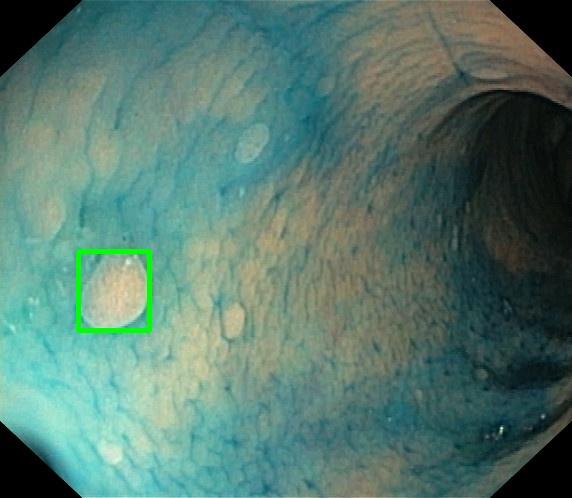

**Final Answer** ``` 用户现在需要解决这个杆系平衡的问题,首先得回忆一下虚位移原理或者能量法,因为涉及到弹簧和力的平衡,可能用虚位移比较方便。首先,先明确系统的自由度,这里AC的距离是x,所以x是广义坐标。当x变化时,整个系统会有虚位移,需要找到各点的虚位移,然后应用虚功原理:所有主动力做的虚功之和为零。 首先,确定弹簧的伸长量。当AC = a时弹簧原长,现在AC = x,所以弹簧的长度变化是多少呢?需要看D和E的位置。因为AB和BC都是长度l,D在AB上,BD = b,所以AD = l - b;E在BC上,BE应该也是b吗?因为杆等长,D和E的位置应该对称,所以BE = b,EC = l - b。所以DE的长度可以用几何关系表示。 当AC = x时,三角形ABC是等腰三角形,AB = BC = l,底边AC = x,所以高h = √(l² - (x/2)²)。D点在AB上,距离B为b,所以D点的坐标可以设A在(0,0),C在(x,0),B在(x/2, h),那么D点的坐标:从B向A移动b长度,AB的方向向量是从B到A:(-x/2, -h),单位向量是(-x/(2l), -h/l),所以D点坐标是B + b*(单位向量) = (x/2 - b*x/(2l), h - b*h/l) = (x/2(1 - b/l), h(1 - b/l))。同理,E点在BC上,距离B为b,BC的方向向量是从B到C:(x/2, -h),单位向量是(x/(2l), -h/l),所以E点坐标是B + b*(单位向量) = (x/2 + b*x/(2l), h - b*h/l) = (x/2(1 + b/l), h(1 - b/l))。 所以DE的长度是E的x坐标减去D的x坐标,因为y坐标相同,所以DE = [x/2(1 + b/l) - x/2(1 - b/l)] = x/2*(2b/l) = xb/l。当AC = a时,DE = a*b/l,此时弹簧原长,所以弹簧的伸长量Δ = DE - (a*b/l) = (xb/l) - (ab/l) = b(x - a)/l。所以弹簧的弹力T = kΔ = kb(x - a)/l,方向是D到E,所以当x > a时,弹簧被拉长,T是拉力。 接下来,应用虚位移原理。主动力有F(作用在C点,水平向右)和弹簧的弹力T(作用在D和E,D受到T向右,E受到T向左,因为弹簧拉力)。需要计算这些力在虚位移下的虚功。 设AC的虚位移为δx(向右为正),那么C点的虚位移是δx(因为C在水平面上,虚位移就是δx)。现在需要找D和E的虚位移,或者找弹簧的虚位移,因为弹簧的虚功是T乘以弹簧长度的虚位移变化。 弹簧的长度DE = xb/l,所以弹簧长度的虚位移δ(DE) = (b/l)δx。弹簧的弹力T是拉力,当弹簧伸长时,弹力做负功(因为力与位移方向相反),所以弹簧的虚功是 -T * δ(DE)(因为T是拉力,弹簧伸长时,D向右,E向左,所以D的虚位移向右,E的虚位移向左,但弹簧的虚位移是DE的增加量,所以弹力T对D做负功,对E也做负功,总和是 -T * δ(DE))。 而力F作用在C点,虚位移是δx,所以F的虚功是F * δx。 根据虚位移原理,所有主动力的虚功之和为零: F * δx - T * δ(DE) = 0 代入T和δ(DE): F * δx - [kb(x - a)/l] * (b/l)δx = 0 因为δx ≠ 0,所以可以约掉: F - [kb²(x - a)]/l² = 0 解得: x - a = (F l²)/(k b²) 所以x = a + (F l²)/(k b²) 不过需要验证一下是否正确,可能哪里出错了? 再检查弹簧长度的计算是否正确。当AC = x时,三角形ABC的底边x,两腰l,所以D和E的位置:D在AB上,BD = b,所以AD = l - b,所以D分AB为AD:DB = (l - b):b,所以D的x坐标(以A为原点,AC为x轴)是 (DB * 0 + AD * x)/AB?不,应该用相似三角形。AB的长度是l,D距离B为b,所以从A到D的距离是l - b,所以D的x坐标是 (l - b)/l * x/2?不对,应该用坐标法更准确。 设A(0,0),C(x,0),B(x/2, h),h = √(l² - (x/2)²) AB的参数方程:从A(0,0)到B(x/2, h),长度l,所以单位向量是 (x/(2l), h/l),所以D点距离A为l - b(因为BD = b,所以AD = AB - BD = l - b),所以D点坐标是 ( (l - b) * x/(2l), (l - b) * h/l ) 同理,BC的参数方程:从B(x/2, h)到C(x,0),长度l,单位向量是 (x/(2l), -h/l),所以E点距离B为b,所以E点坐标是 B + b*(单位向量) = (x/2 + b*x/(2l), h - b*h/l ) = ( (l + b)x/(2l), (l - b)h/l ) 所以D点坐标是 ( (l - b)x/(2l), (l - b)h/l ) E点坐标是 ( (l + b)x/(2l), (l - b)h/l ) 所以DE的长度是 E_x - D_x = [ (l + b)x/(2l) - (l - b)x/(2l) ] = (2b x)/(2l) = b x / l,对的,之前的计算是对的。 当AC = a时,DE = b a / l,此时弹簧原长,所以弹簧伸长量是 DE - (b a / l) = b(x - a)/l,正确。 弹簧的弹力T = k * 伸长量 = k b (x - a)/l,正确。 现在虚位移:当AC有虚位移δx时,DE的长度变化δ(DE) = b/l δx,正确。 力F作用在C点,虚位移δx,虚功F δx。 弹簧的弹力:D点受到T向右(因为弹簧拉D向右),E点受到T向左(弹簧拉E向左)。D点的虚位移:D点的x坐标是 (l - b)x/(2l),所以虚位移δ(D_x) = (l - b)/(2l) δx,方向向右;E点的x坐标是 (l + b)x/(2l),虚位移δ(E_x) = (l + b)/(2l) δx,方向向右。 所以弹簧对D的虚功是 T * δ(D_x)(因为T向右,D的虚位移向右,所以正功?不,弹簧拉力是D受到向右的力,当D向右移动时,力与位移同方向,做正功;E受到向左的力,E向右移动,所以力与位移反方向,做负功。所以总虚功是 T * δ(D_x) - T * δ(E_x) = T [ (l - b)/(2l) - (l + b)/(2l) ] δx = T [ (-2b)/(2l) ] δx = -T (b/l) δx,和之前的结果一致,即 -T * δ(DE),因为δ(DE) = δ(E_x) - δ(D_x) = (b/l)δx,所以弹簧的虚功是 -T * δ(DE),正确。 所以虚功方程:F δx - T (b/l) δx = 0 → F = T (b/l) 代入T = k b (x - a)/l,得 F = [k b (x - a)/l] * (b/l) = k b² (x - a)/l² 所以x - a = F l² / (k b²) → x = a + F l² / (k b²) 这样应该是对的。再考虑能量法,系统的势能包括弹簧的弹性势能和力F做的功(因为F是主动力,可以视为保守力,势能为 -F x)。平衡时势能取极值,即dU/dx = 0。 弹性势能U_spring = (1/2)k (Δ)^2 = (1/2)k [b(x - a)/l]^2 力F的势能U_F = -F x(因为F是向右的力,位移x增加时,F做正功,势能减少) 总势能U = U_spring + U_F = (1/2)k b² (x - a)^2 / l² - F x 求导dU/dx = (k b² / l²)(x - a) - F = 0 → x = a + F l² / (k b²),和虚位移原理结果一致,正确。 所以距离AC的值是a + (F l²)/(k b²)。 ### 问题分析 本题涉及一个由两根等长杆 $ AB $ 和 $ BC $ 构成的系统,它们在点 $ B $ 处通过铰链连接。在杆上分别取点 $ D $(位于 $ AB $ 上)和点 $ E $(位于 $ BC $ 上),并用一根弹簧连接。当底边 $ AC = a $ 时,弹簧处于自然长度(无拉力)。在点 $ C $ 施加一水平力 $ F $,使整个系统处于平衡状态。 目标是求出此时底边 $ AC $ 的长度 $ x $。 --- ### 解题思路 #### 1. **几何关系与弹簧伸长量** - 杆 $ AB = BC = l $ - 点 $ D $ 距离 $ B $ 为 $ b $,因此 $ AD = l - b $ - 点 $ E $ 距离 $ B $ 也为 $ b $,因此 $ BE = b $ 设 $ AC = x $,则三角形 $ ABC $ 是等腰三角形,其高为: $$ h = \sqrt{l^2 - \left(\frac{x}{2}\right)^2} $$ 利用相似三角形可得: - 点 $ D $ 的横坐标为:$ \frac{(l - b)}{l} \cdot \frac{x}{2} $ - 点 $ E $ 的横坐标为:$ \frac{(l + b)}{l} \cdot \frac{x}{2} $ 因此,弹簧长度 $ DE $ 为: $$ DE = \frac{b x}{l} $$ 当 $ AC = a $ 时,弹簧长度为 $ \frac{b a}{l} $,即为自然长度。故弹簧的伸长量为: $$ \Delta = \frac{b(x - a)}{l} $$ 弹簧弹力为: $$ T = k \Delta = \frac{k b (x - a)}{l} $$ --- #### 2. **虚位移原理** 设 $ AC $ 的虚位移为 $ \delta x $,则: - 点 $ C $ 的虚位移为 $ \delta x $ - 弹簧长度的虚位移为: $$ \delta(DE) = \frac{b}{l} \delta x $$ 主动力包括: - 水平力 $ F $,作用于点 $ C $,虚功为 $ F \delta x $ - 弹簧弹力 $ T $,对系统做负功,虚功为 $ -T \cdot \delta(DE) $ 根据虚位移原理,所有主动力的虚功之和为零: $$ F \delta x - T \cdot \frac{b}{l} \delta x = 0 $$ 代入 $ T = \frac{k b (x - a)}{l} $ 得: $$ F \delta x - \frac{k b^2 (x - a)}{l^2} \delta x = 0 $$ 约去 $ \delta x $(因 $ \delta x \neq 0 $): $$ F = \frac{k b^2 (x - a)}{l^2} $$ 解得: $$ x - a = \frac{F l^2}{k b^2} $$ --- ### 最终答案 $$ \boxed{x = a + \frac{F l^2}{k b^2}} $$ ``` ## Case 6 · Medical — Endoscopy Diagnosis **Source:** GMAI-MMBench_VAL **Question:** > Focus on the square-highlighted area of this endoscopy image. What could be the potential diagnosis? > > A. Barrett's esophagus   B. Gastrointestinal tract cancer   C. High-grade dysplasia   D. Polyp **Input Image**

Endoscopy image with square-highlighted lesion

**Model Reasoning** ``` Got it, let's try to figure out this endoscopy image. First, let's recall what each option means. Barrett's esophagus is a condition where the normal squamous epithelium of the esophagus is replaced by columnar epithelium, often due to chronic acid reflux. It's usually seen in the lower esophagus and might have a salmon-colored appearance, but the image here has a blue dye, which is often used in chromoendoscopy for better visualization. Gastrointestinal tract cancer—this is a broad term, but esophageal cancer might present with irregular lesions, but the highlighted area here looks like a raised lesion, maybe a polyp? High-grade dysplasia is a precancerous condition, often associated with Barrett's esophagus. It's more about cellular changes rather than a visible lesion like a polyp. Polyp: in the GI tract, polyps are growths that protrude from the mucosal surface. In endoscopy, they can be seen as raised lesions. The green square highlights a rounded, raised area, which is typical of a polyp. Wait, but let's check the context. The image is from an endoscopy, and the blue dye might be used for chromoendoscopy, which can help identify abnormalities. But the highlighted area is a distinct, rounded lesion. Polyps are common findings in endoscopy, especially in the colon, but this could be in the esophagus or stomach. However, the options include polyp as D. Barrett's esophagus is more about the mucosal change, not a discrete polypoid lesion. High-grade dysplasia is a histological diagnosis, not a visible lesion per se. Gastrointestinal cancer would be more invasive, with irregular borders, ulceration, etc. The highlighted area looks like a benign polyp, which is a common finding. So the answer is D. ``` **Final Answer** $$\boxed{D.\ \text{Polyp}}$$ # Cases: Thinking with Images ## Case 1 · Mathematics — Calendar Reasoning **Source:** MathVision  |  **Tool used:** Circular diagram annotation **Question:** > Emily celebrated her birthday on Thursday, and her sister Liepa 8 days earlier. Which weekday was that? > (A) Wednesday   (B) Thursday   (C) Friday   (D) Tuesday   (E) Sunday **Input Image**